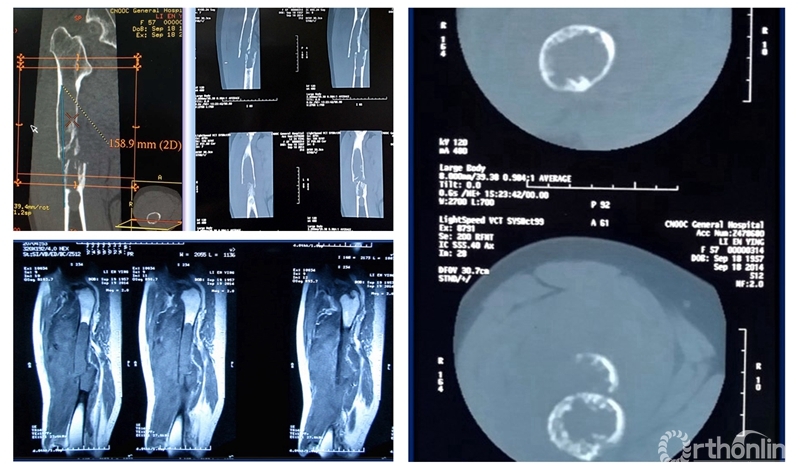

患者女性,68岁,乳腺癌病史,右股骨中段病理性骨折,股骨长段溶骨性破坏,并有跳跃病灶。病变的长度为16cm,病灶近端在小转移水平,因为近端髓腔柄较短,故选择A区骨干假体。经病理诊断为转移性腺癌,术后2周患者拆线后即可离床活动。

术前资料